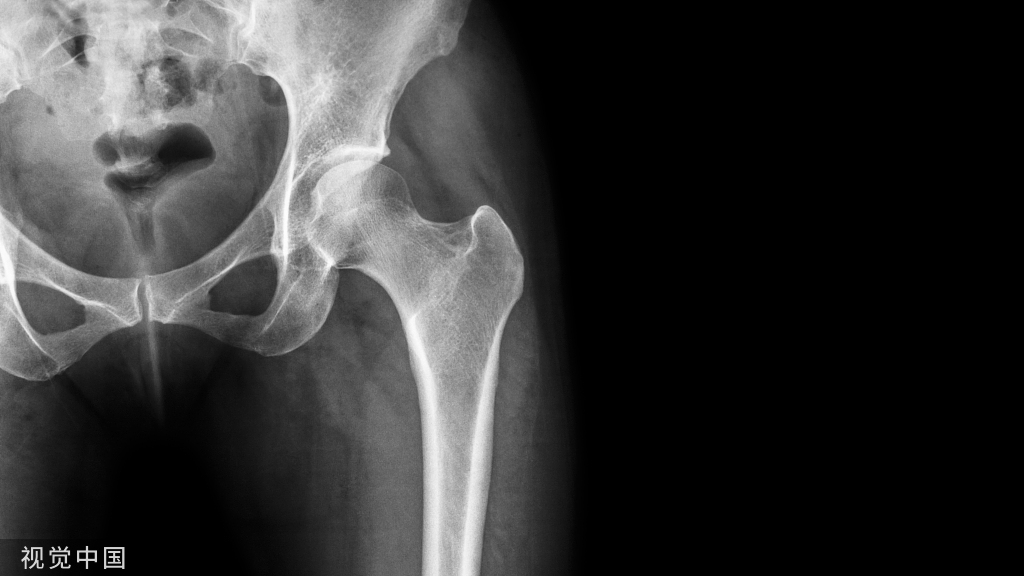

弥散性血管内凝血(DIC)是一种涉及凝血系统的全身性疾病,同时激活促凝血级联、纤维蛋白溶解和消耗性凝血病的发展。它最终可能导致休克、多器官功能障碍和死亡。DIC 是一种后天性疾病,最常与恶性肿瘤和败血症相关。其他原因包括外伤、肝病、胰腺炎、输血反应、产科疾病和手术。无论何种原因,预后都是严峻的。虽然罕见,但也有零星的骨科手术后发生 DIC 的病例报告,其中大量发生在已知恶性肿瘤的情况下,多见于髋部骨折或关节置换等。

其发病率随潜在的诱发危险因素而变化。恶性肿瘤是骨科手术中的一个重要危险因素。文献报道多数发生在手术中发生转移性病理性骨折中。也有报道称,在没有已知危险因素的患者中接受选择性脊柱手术和复杂的髋部手术,可能手术时间长且术中失血量大。

在骨科手术中,脂肪栓塞和肿瘤栓塞的释放可引发 DIC 。骨折、髓质扩髓和胶结释放的脂肪栓塞闭塞小血管,产生瘀滞和细胞缺氧损伤,易于凝血。血浆中的脂肪栓子被脂肪酶分解成游离脂肪酸,这进一步损害内皮细胞并可能引发凝血级联反应。脂肪栓塞还通过血管闭塞和肿瘤坏死因子 α等血管舒张细胞因子直接加剧 DIC 中的多器官损伤和低血压。在骨科手术中对转移部位的操作,例如对即将发生的病理性骨折进行扩孔或对脊柱转移瘤进行减压,也可以将肿瘤栓子释放到体循环中。这些栓子中的肿瘤细胞表达组织因子,从而触发凝血级联反应 。正如脊柱手术中经常进行的那样,为了获得移植材料而进行的骨质剥离被认为会暴露大量的原始表面以接触激活凝血系统。围手术期体温过低和低血压也可能导致手术患者发生 DIC。